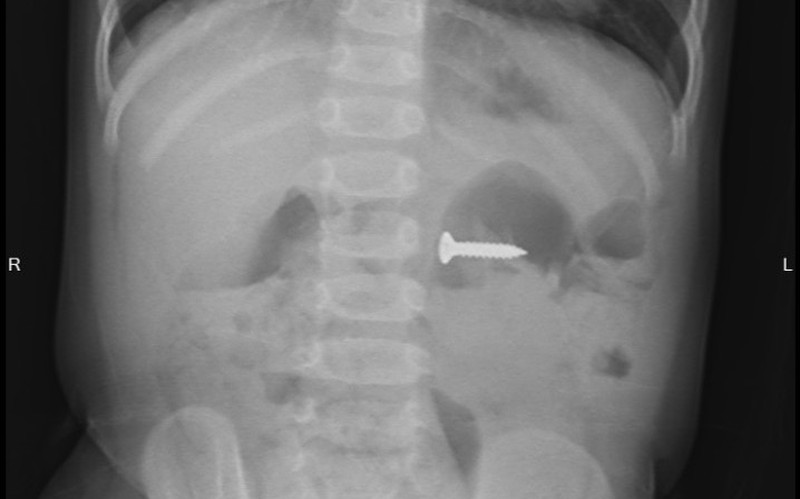

Tại Bệnh viện Sản Nhi tỉnh Phú Thọ, các bác sĩ chỉ định cho bé chụp X-quang thăm dò và phát hiện dị vật đinh vít kích thước 2cm trong dạ dày, vị trí ngang đốt sống D3. Sau khi hội chẩn với các bác sĩ Khoa Ngoại nhi tổng hợp và giải thích với gia đình, bé được chỉ định gây mê nội soi tiêu hóa cấp cứu gắp dị vật.

Sau 5 phút, BSCKI.Triệu Ngọc Bích, Khoa Chẩn đoán hình ảnh – thăm dò chức năng gắp ra được dị vật là 1 chiếc đinh ốc vít có một đầu sắc nhọn nằm trong dạ dày của bé. Các bác sĩ đánh giá, với tính chất sắc nhọn của đầu đinh, nếu không loại bỏ kịp thời có thể gây tổn thương đâm thủng thành ruột, dạ dày, thậm chí có thể gây tổn thương nhiều vị trí mà chiếc đinh đi qua.